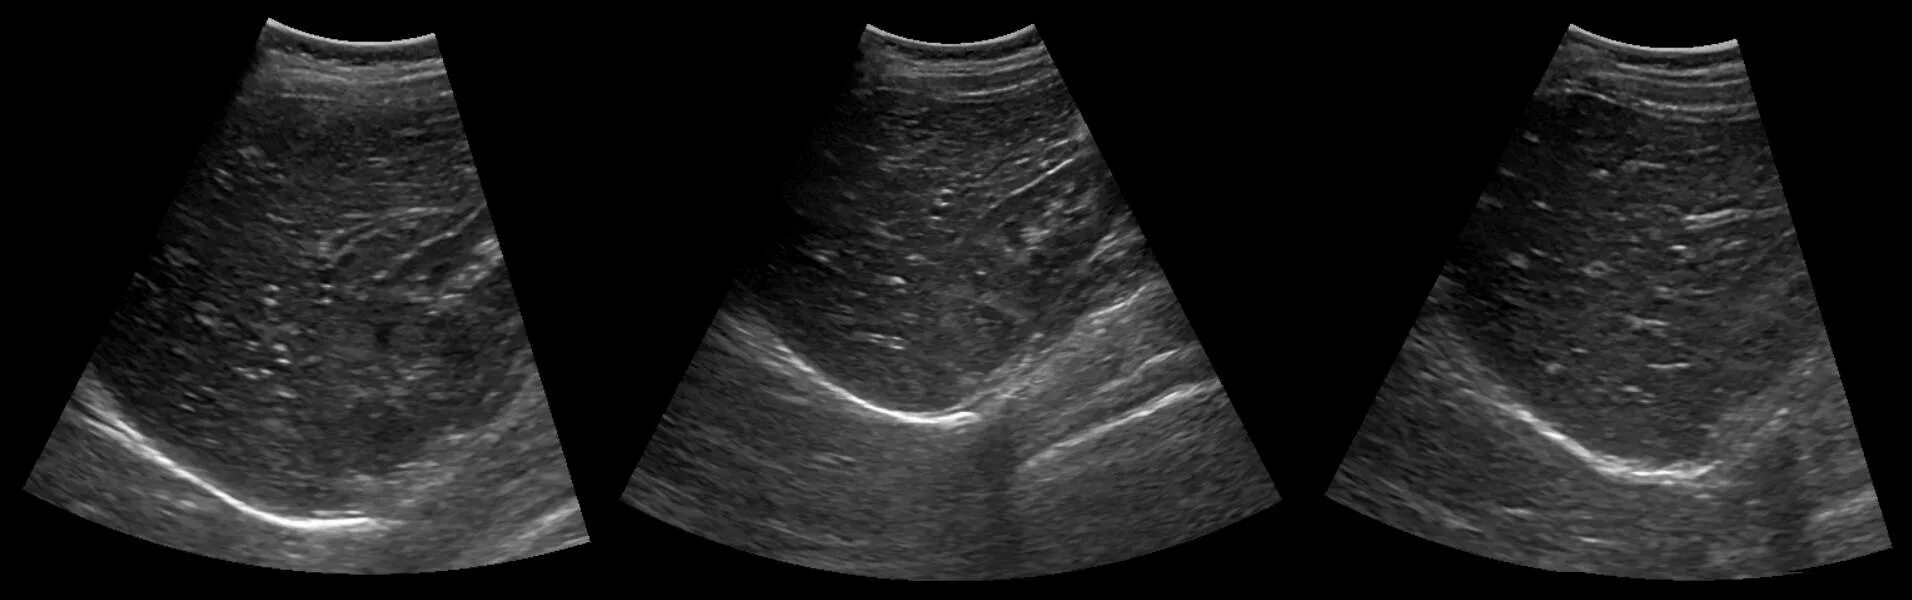

Диффузно жировые изменения печени